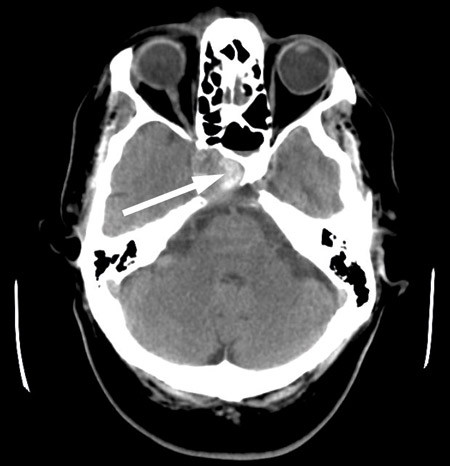

Cerebral CT og CT-angiografi like etter innleggelsen viste ikke tegn til blødning, men man fant på høyre side et intrakavernøst carotisaneurisme med diameter på 10 mm og en beineroderende prosess i sfenoidalsinus og clivus (fig 1, fig 2). MR-undersøkelse av hodet med og uten kontrast bekreftet et aneurisme i mediale del av sinus cavernosus på høyre side og beindestruksjon i samme område (fig 3).

MR-undersøkelsen og funnet av beindestruksjon ga mistanke om en kronisk sinusitt i sfenoidalsinus, og kombinasjonen av beindestruksjon og aneurisme kunne tyde på mulig aspergillusinfeksjon med mykotisk aneurisme på a. carotis interna i skallebasis. Beindestruksjon i sfenoidalsinus er forbundet med stor fare for ekstrem epistaxis, og vi kjenner til dødsfall som følge av epistaxis via sfenoidalsinus fra et tilsvarende aneurisme.